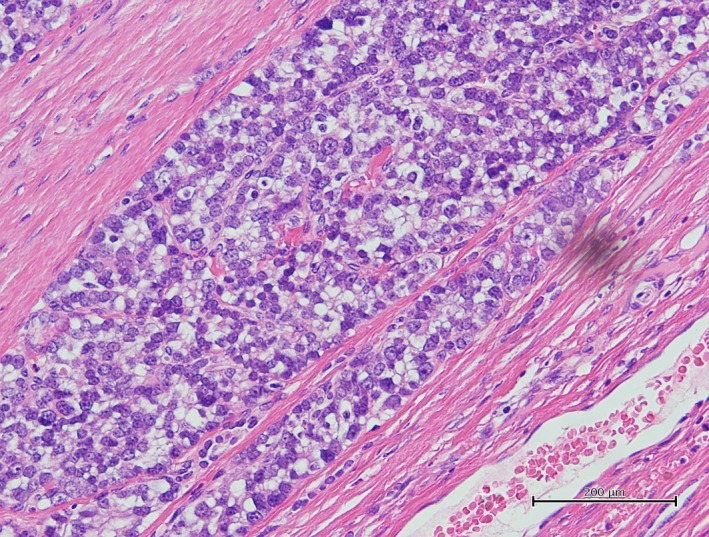

A 19‐year‐old girl who had a complaint of a swollen and enlarged feeling of her cervical mass for a few months visited our hospital (Figure 1). The patient had no particular past or family history including thyroidal disorders or other neoplasms. Cervical examination by ultrasonography revealed a diffusely enlarged left thyroid tumor showing a heterogenous pattern without clear capsule formation (Figure 2A), in which internal blood flow was augmented by a Doppler scan (Figure 2B). Endocrine examination showed that the patient was euthyroid and there were no thyroid autoantibodies (Table 1). A chest X‐ray showed a tracheal shift to the right and a dense shadow of the neck (Figure 3A). Computed tomography showed enlargement of the left thyroidal lesion and airway constriction (Figure 3B, coronal view; Figure 3C, horizontal view). Based on the results of cytology of a fine‐needle aspiration specimen, a follicular neoplasm was suspected. Left thyroidectomy was then performed, and a pathological diagnosis of follicular carcinoma (pT3N0M0 pStage I) was made on the basis of examination of the resected thyroid lesion (Figure 4). Cancer recurrence was not observed for a period of 1 year after surgery.

Figure 4.

Pathology of the resected thyroid tumor stained with hematoxylin and eosin showed proliferation of heteromorphic follicular carcinoma cells with capsular invasion